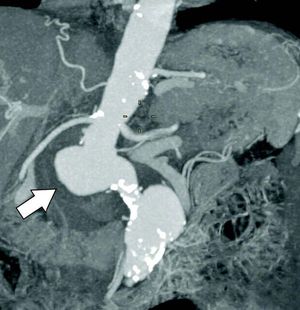

This CT scan is from a 77-year-old woman with abdominal aortitis and impending aneurysm rupture. What is the most likely clinical presentation of the patient? 1) AIDS with pulmonary tuberculosis 2) Bacterial meningitis 3) Intermittent claudication 4) Neurosyphilis

It is intermittent claudication means obstruction of arteries